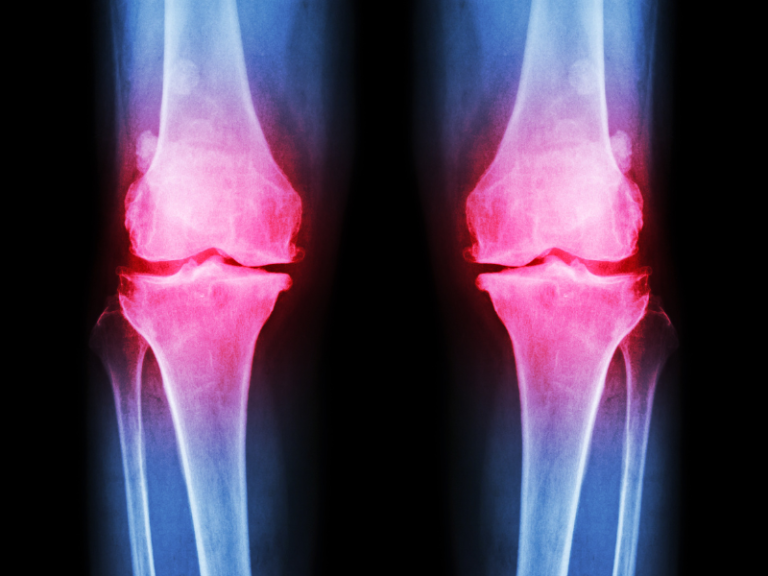

La artrosis es una enfermedad que afecta las articulaciones. En España, algunas zonas son mejores que otras para vivir con esta condición. Vamos a ver cómo podemos identificar los mejores lugares.